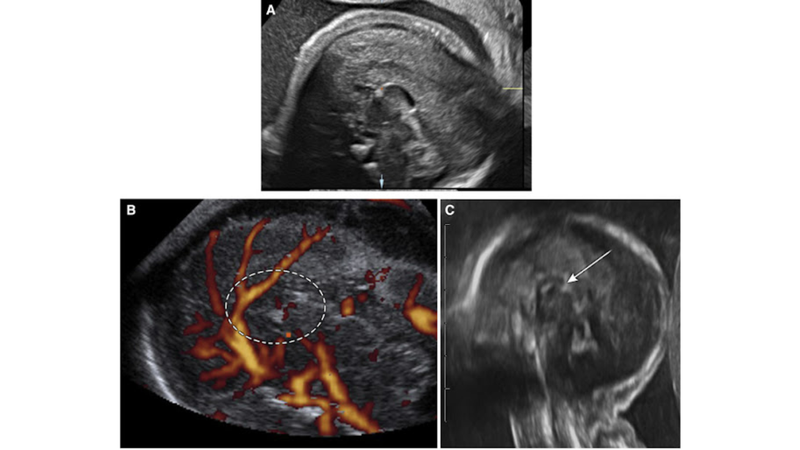

ACC thường được chẩn đoán thông qua các kỹ thuật hình ảnh như chụp cộng hưởng từ (MRI) hoặc chụp cắt lớp vi tính (CT). Các phương pháp này giúp bác sĩ nhìn thấy sự hiện diện hoặc thiếu vắng của thể chai.

Thời gian phát hiện ACC thường từ tuần thứ 18 của thai kỳ. Một số nghiên cứu mới đã chỉ ra rằng các dấu hiệu sớm có thể được phát hiện từ tuần thứ 13. Ở Việt Nam, bất sản thể chai thường được phát hiện trong giai đoạn siêu âm hình thái quý 2 từ tuần thứ 20 đến 22.

Siêu âm hệ thần kinh chi tiết hoặc MRI từ tuần thứ 30 đến 32, nhằm phát hiện thêm các bất thường khác, đặc biệt là nhóm bất thường phát triển vỏ não.